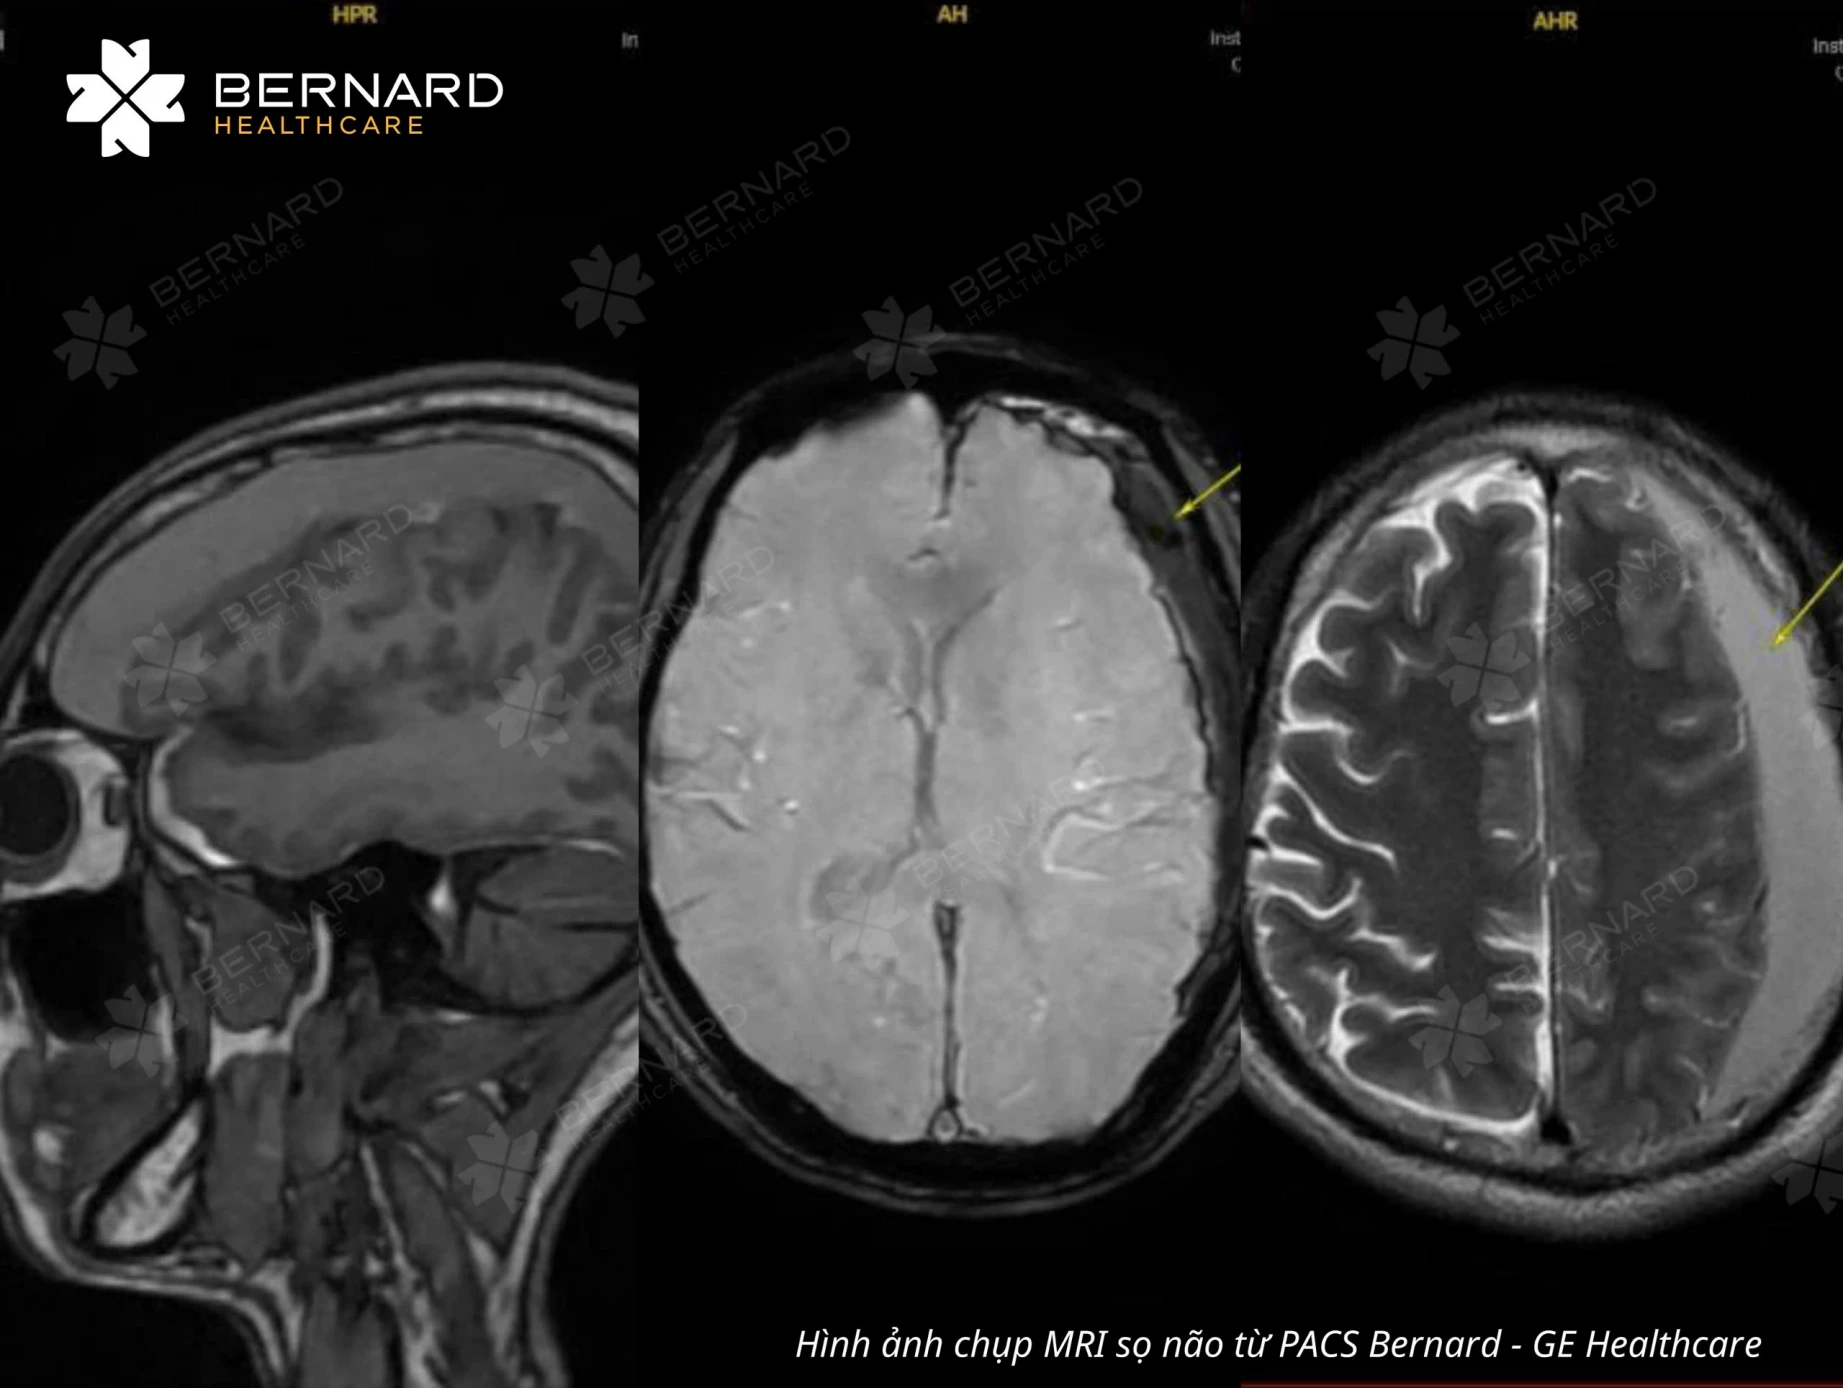

Kết quả MRI ghi nhận đồng thời nhiều dấu hiệu nguy hiểm. Bệnh nhân có tụ máu dưới màng cứng bán cầu não trái, dọc liềm não và lều tiểu não trái, bề dày khối máu tụ dmax khoảng 18mm.

Khối máu tụ đã ép não thất bên trái, khiến đường giữa lệch nhẹ sang phải. Dấu hiệu của khối máu tụ nhiều giai đoạn (cấp - bán cấp), cho thấy tình trạng đã tồn tại một thời gian dài.

Khi có kết quả MRI, Bernard Healthcare kích hoạt quy trình xử trí ca nguy cơ cao. Tiến sĩ - Bác sĩ CKII Nguyễn Đại Hùng Linh, phụ trách Chuyên khoa Chẩn đoán hình ảnh Bernard mô tả chi tiết vị trí, giai đoạn của máu tụ, mức độ đè ép nhu mô và lệch đường giữa, những thông số quyết định người bệnh cần can thiệp ngoại khoa hay theo dõi.